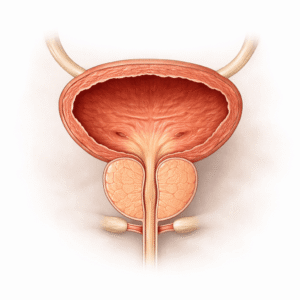

Eturauhasterveys

Prostataterveyden Ymmärtäminen Prostata on pieni rauhanen, joka sijaitsee virtsarakon alapuolella…

Prostatahyveyden salaisuudet: Mikä on oikeasti hyväksi sinulle!

Prostataongelmat voivat aiheuttaa kamalaa epämukavuutta, mutta ymmärtäminen siitä, mikä on hyväksi eturauhasen…

Eturauhasen terveys: Vinkkejä hyvinvointiin

Prostata terveys ei usein saa ansaitsemaansa huomiota ennen kuin siitä tulee ongelma.…

Mikä on oikeasti hyvää eturauhasen terveydelle? Testaa tietosi

Eturauhasterveys: Oireet, Uni, PSA ja Hyvät Tavat